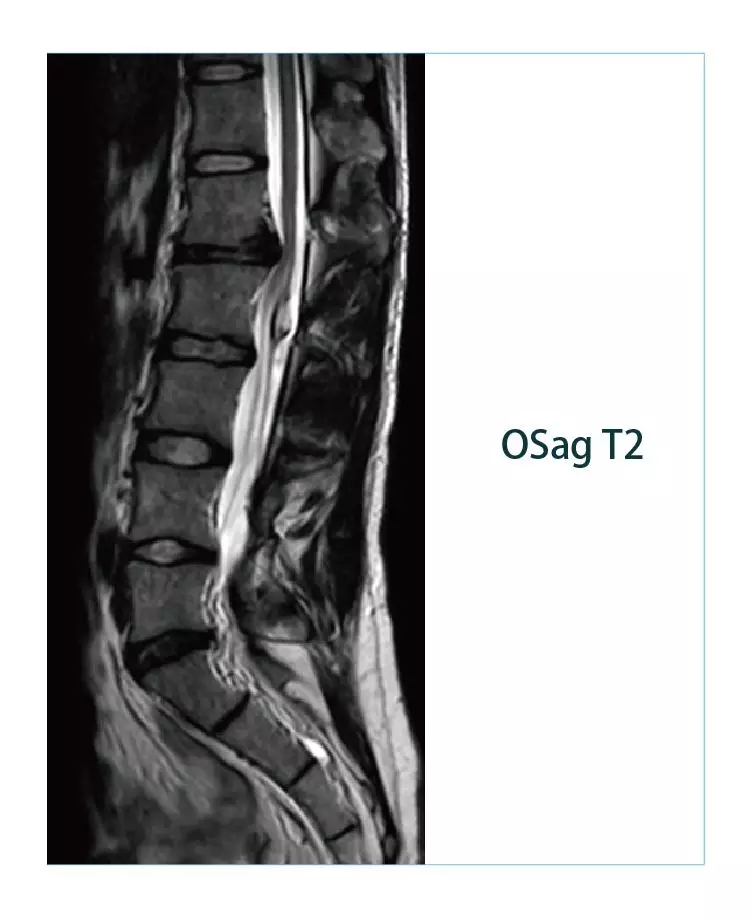

【朗润影像档案】磁共振影像病例分享(编号20190225)

1551142369809397.jpg1551142384228370.jpg